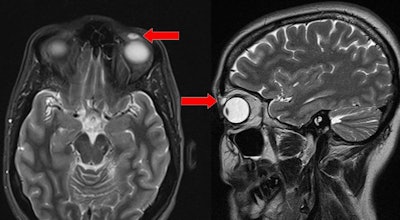

An MRI scan of the orbit was performed, and it revealed a well-defined ovoid nodule measuring 8 x 4 x 6 mm. Features on the MRI scan were consistent with a cyst with proteinaceous content, Patel and colleagues reported. There were no other features of any foreign body.

The nodule was excised and found to be an encapsulated cyst. Upon further investigation, the cyst ruptured and the clinicians extracted a rigid gas permeable (RGP) contact lens.

They credited MRI with a radiofrequency surface coil as key to helping them detect the lens, thanks to the imaging modality's submillimeter resolution.

"This alternative method of imaging may have provided better visualization of the eyelid anatomy and possibly identified the foreign RGP lens in situ," they concluded.